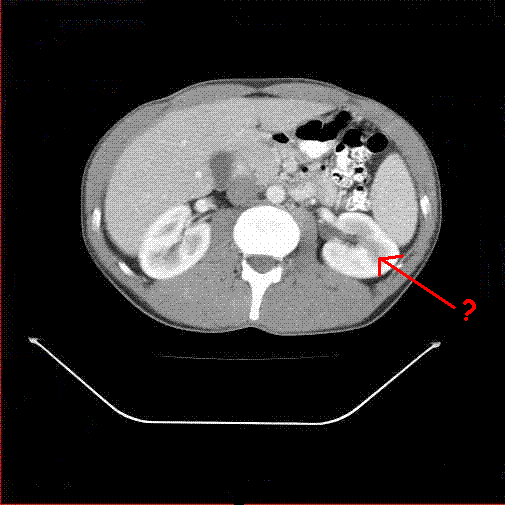

What structure is this?

This structure is the left kidney.